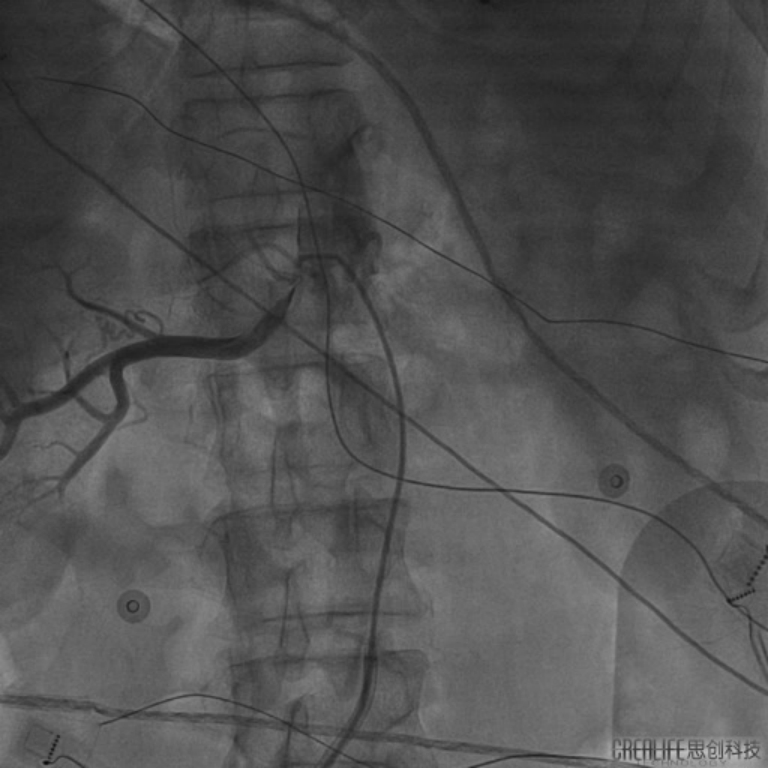

在充分考虑患者及其家属意愿后,汤宝鹏教授及李耀东教授经过术前讨论为患者量身定制了缜密的手术方案。手术由李耀东教授主刀采用导管微创介入手术,通过在X线下对左右肾动脉血管进行造影定位,同时在三维可视系统的指导下对肾动脉进行三维重建并进行射频消融。消融治疗通过在患者右腿植入一根直径大约2.5mm的管路进行,每次消融仅需30秒,18次治疗的手术过程约一个小时,且患者全程保持清醒,显著提升了患者的治疗体验。

(图为手术过程中对患者进行肾动脉造影定位)